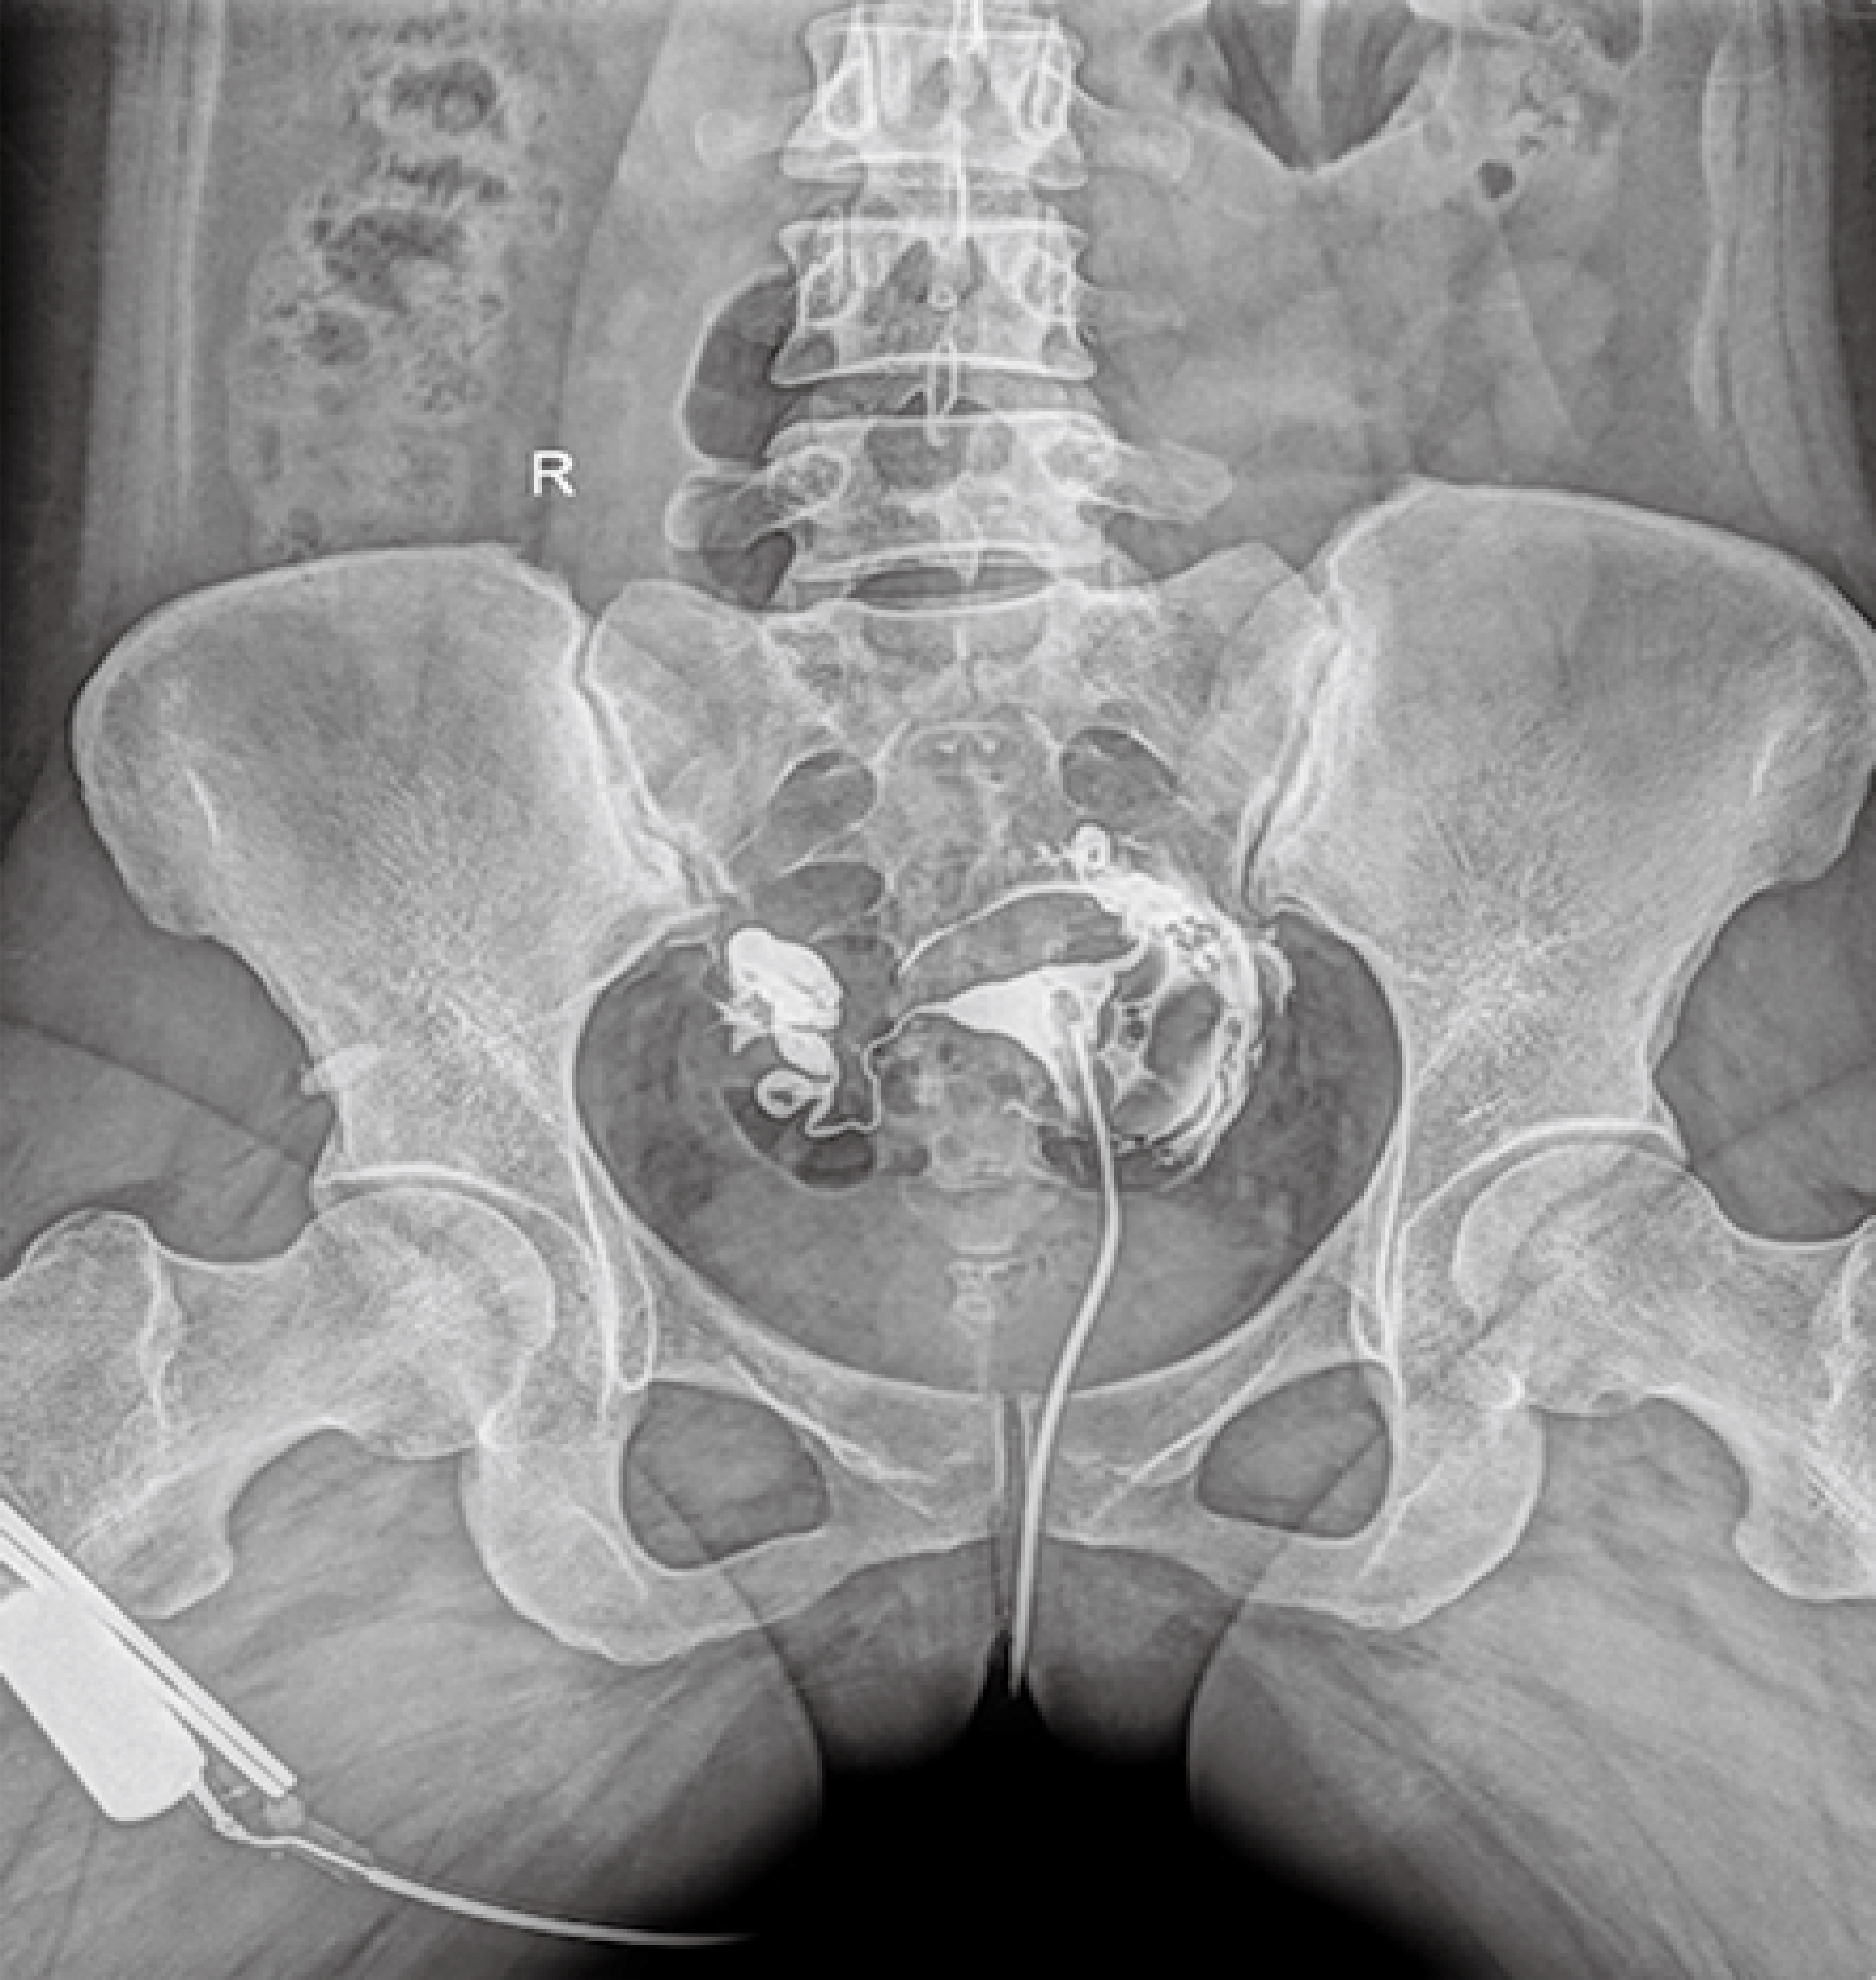

普利德醫(yī)療自主研發(fā)的新一代數(shù)字化X線透視攝影系統(tǒng),可應用于DR攝影、數(shù)字透視、數(shù)字造影以及可視化精準DR拍片等多種臨床X線檢查領域。

● 高效動態(tài)平板技術,圖像不會有幾何畸變,提供高分辨率和精確的圖像,為醫(yī)生臨床診斷提供精準依據(jù);

● 最高幀速可達30幀/秒,動態(tài)采集清晰流暢,避免漏診、誤診情況的發(fā)生;

● 在可視過程或回放過程中,如發(fā)現(xiàn)疑似病灶,可進行毫秒級高清點片,隨時抓取單幀圖像,精準捕抓病灶。